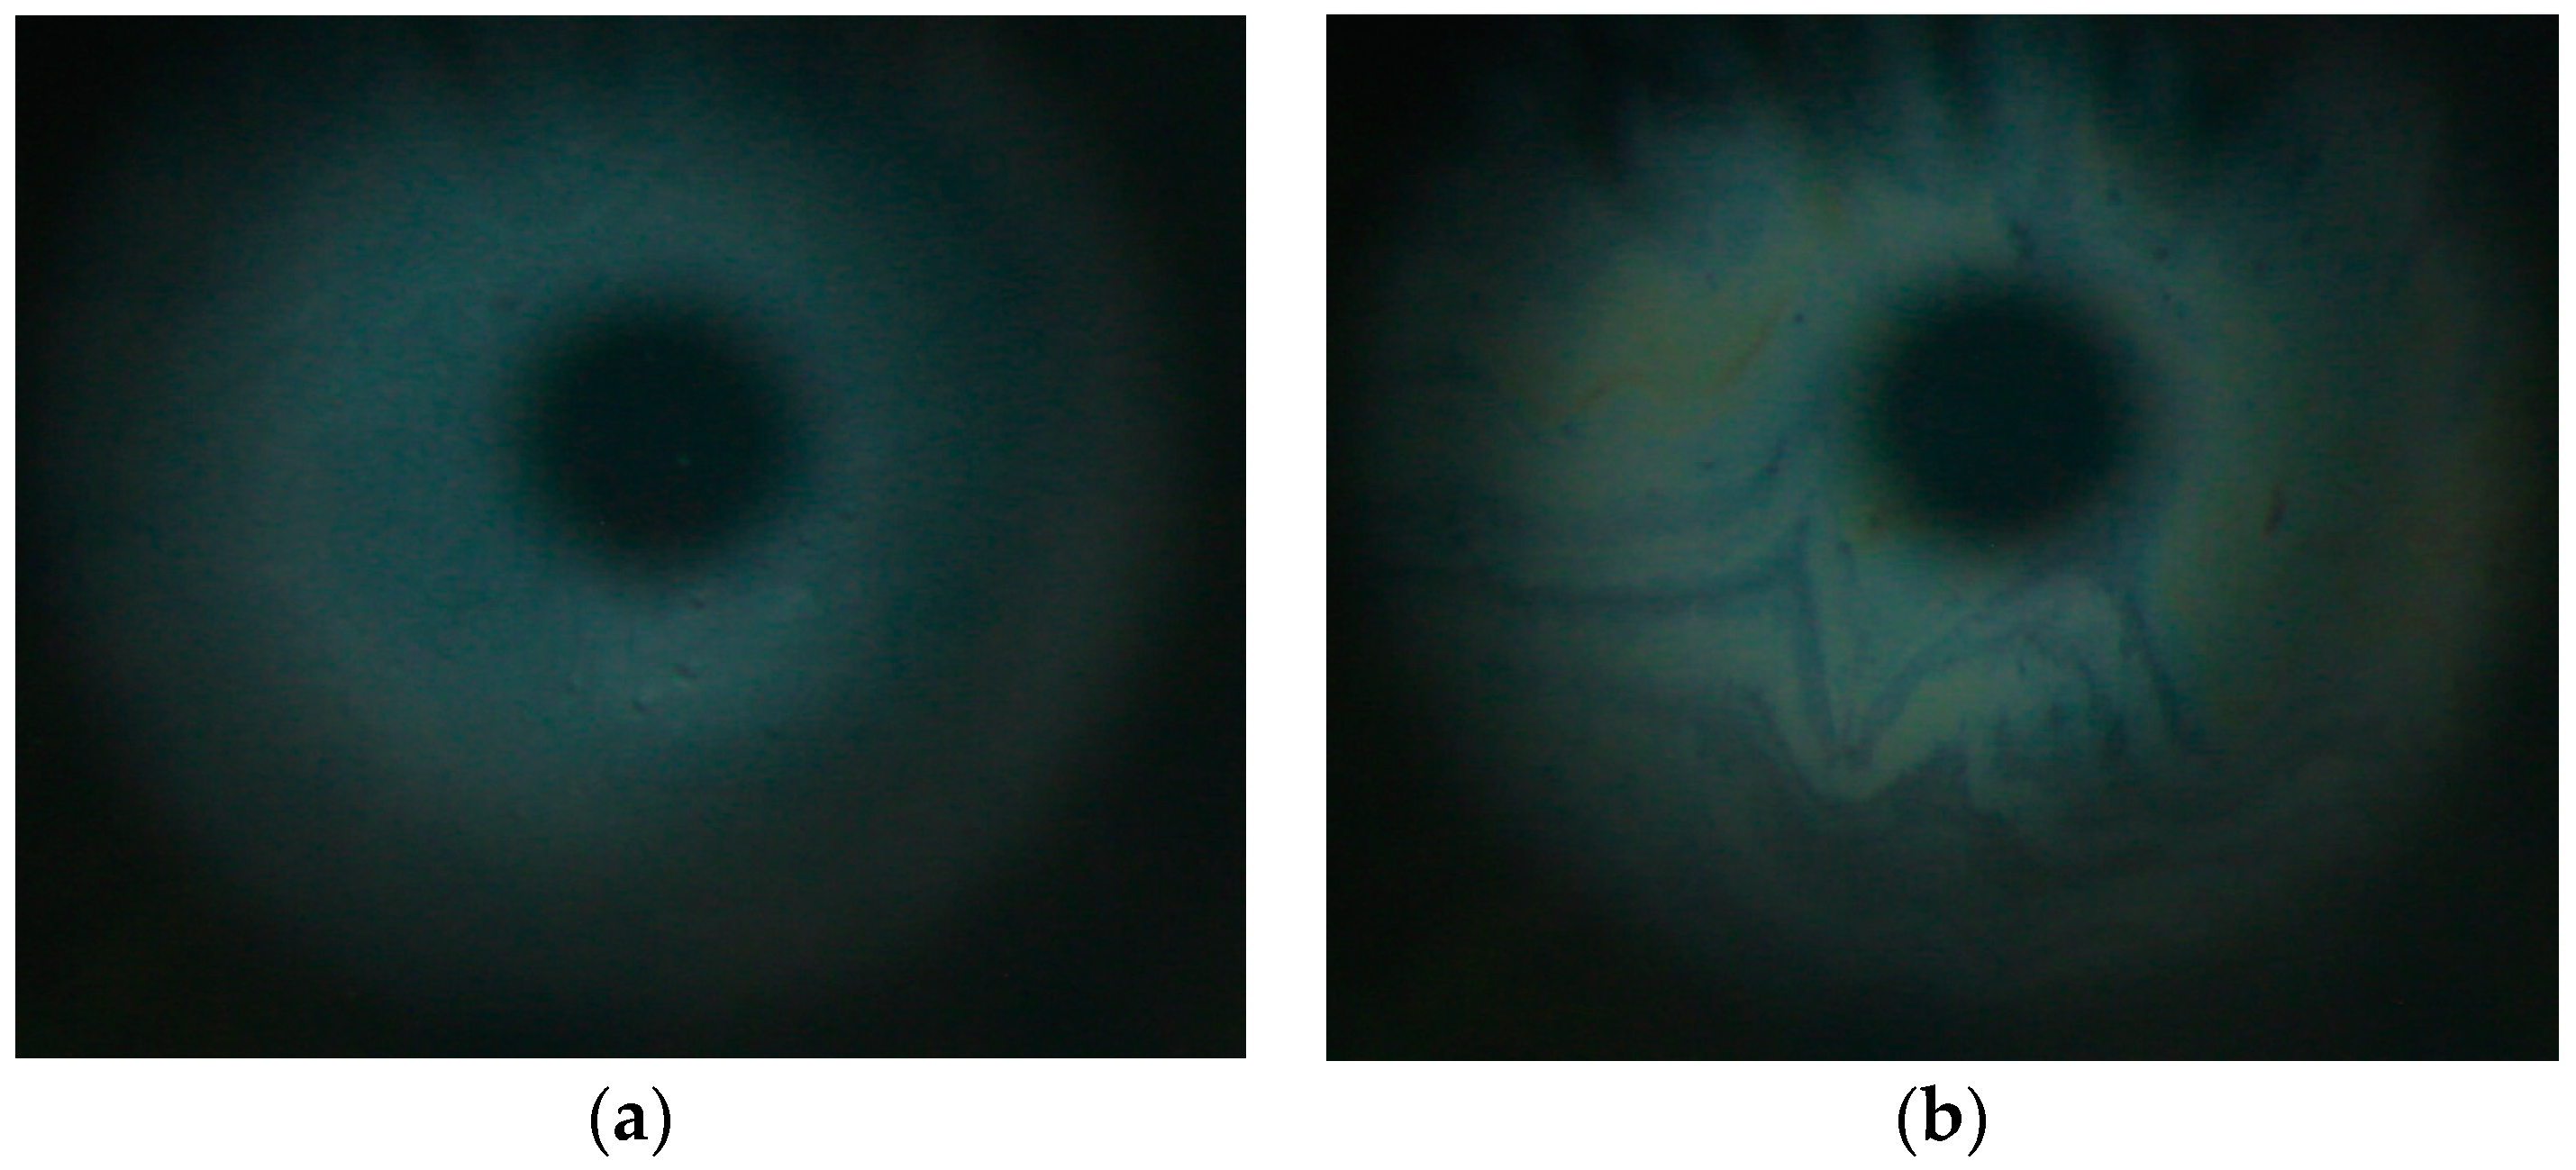

3.1. Surface Pressure Area/Isocycles of nMGS and dMGS Films and Their Morphology as Visualized by Brewster Angle Microscopy

3.2. Effect of Rohto Dry Aid on dMGS Films